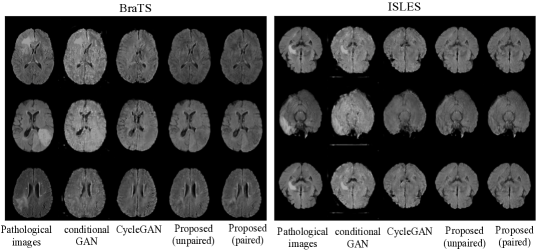

We train our proposed method in both paired and unpaired settings on ISLES and BraTS datasets, and compare with the baselines of Section 4.1. Some results can be seen in Figure 4, where we observe that all synthetic images visually appear to be healthy. However, the pseudo healthy images generated by conditional GAN are blurry and to some degree different from the original samples, i.e. the lateral ventricles (cavities in the middle) change: a manifestation of loss of ‘identity’. Similarly, we observe changes of lateral ventricles in the synthetic images generated by CycleGAN. These changes are probably due to the fact that CycleGAN needs to hide information to reconstruct the input images. We also observe that our methods preserve more details of the original samples. Together, these observations imply that our proposed methods maintain better ‘identity’ than the baselines.

Refer to caption

Figure 4: Experimental results for BraTS and ISLES data are shown in the left and right part respectively. Each part shows three samples (in three rows). The columns from left to right show the ground-truth pathological images, and pseudo healthy images generated by conditional GAN, CycleGAN, and the two proposed methods, respectively.

We also use the proposed evaluation metrics to measure the quality of synthetic images generated by our method and baselines, respectively. The numerical results are shown in Table 1. We can see that our proposed method (paired) when trained using pathological image and mask pairs achieves the best results, followed by our proposed method (unpaired). Both paired and unpaired versions outperform conditional GAN and CycleGAN in both the BraTS and ISLES datasets. The improvements of our method are due to the factorization of pathology, which ensures maintaining information of the pathology during the pseudo healthy synthesis such that the synthetic images do not need to hide information.